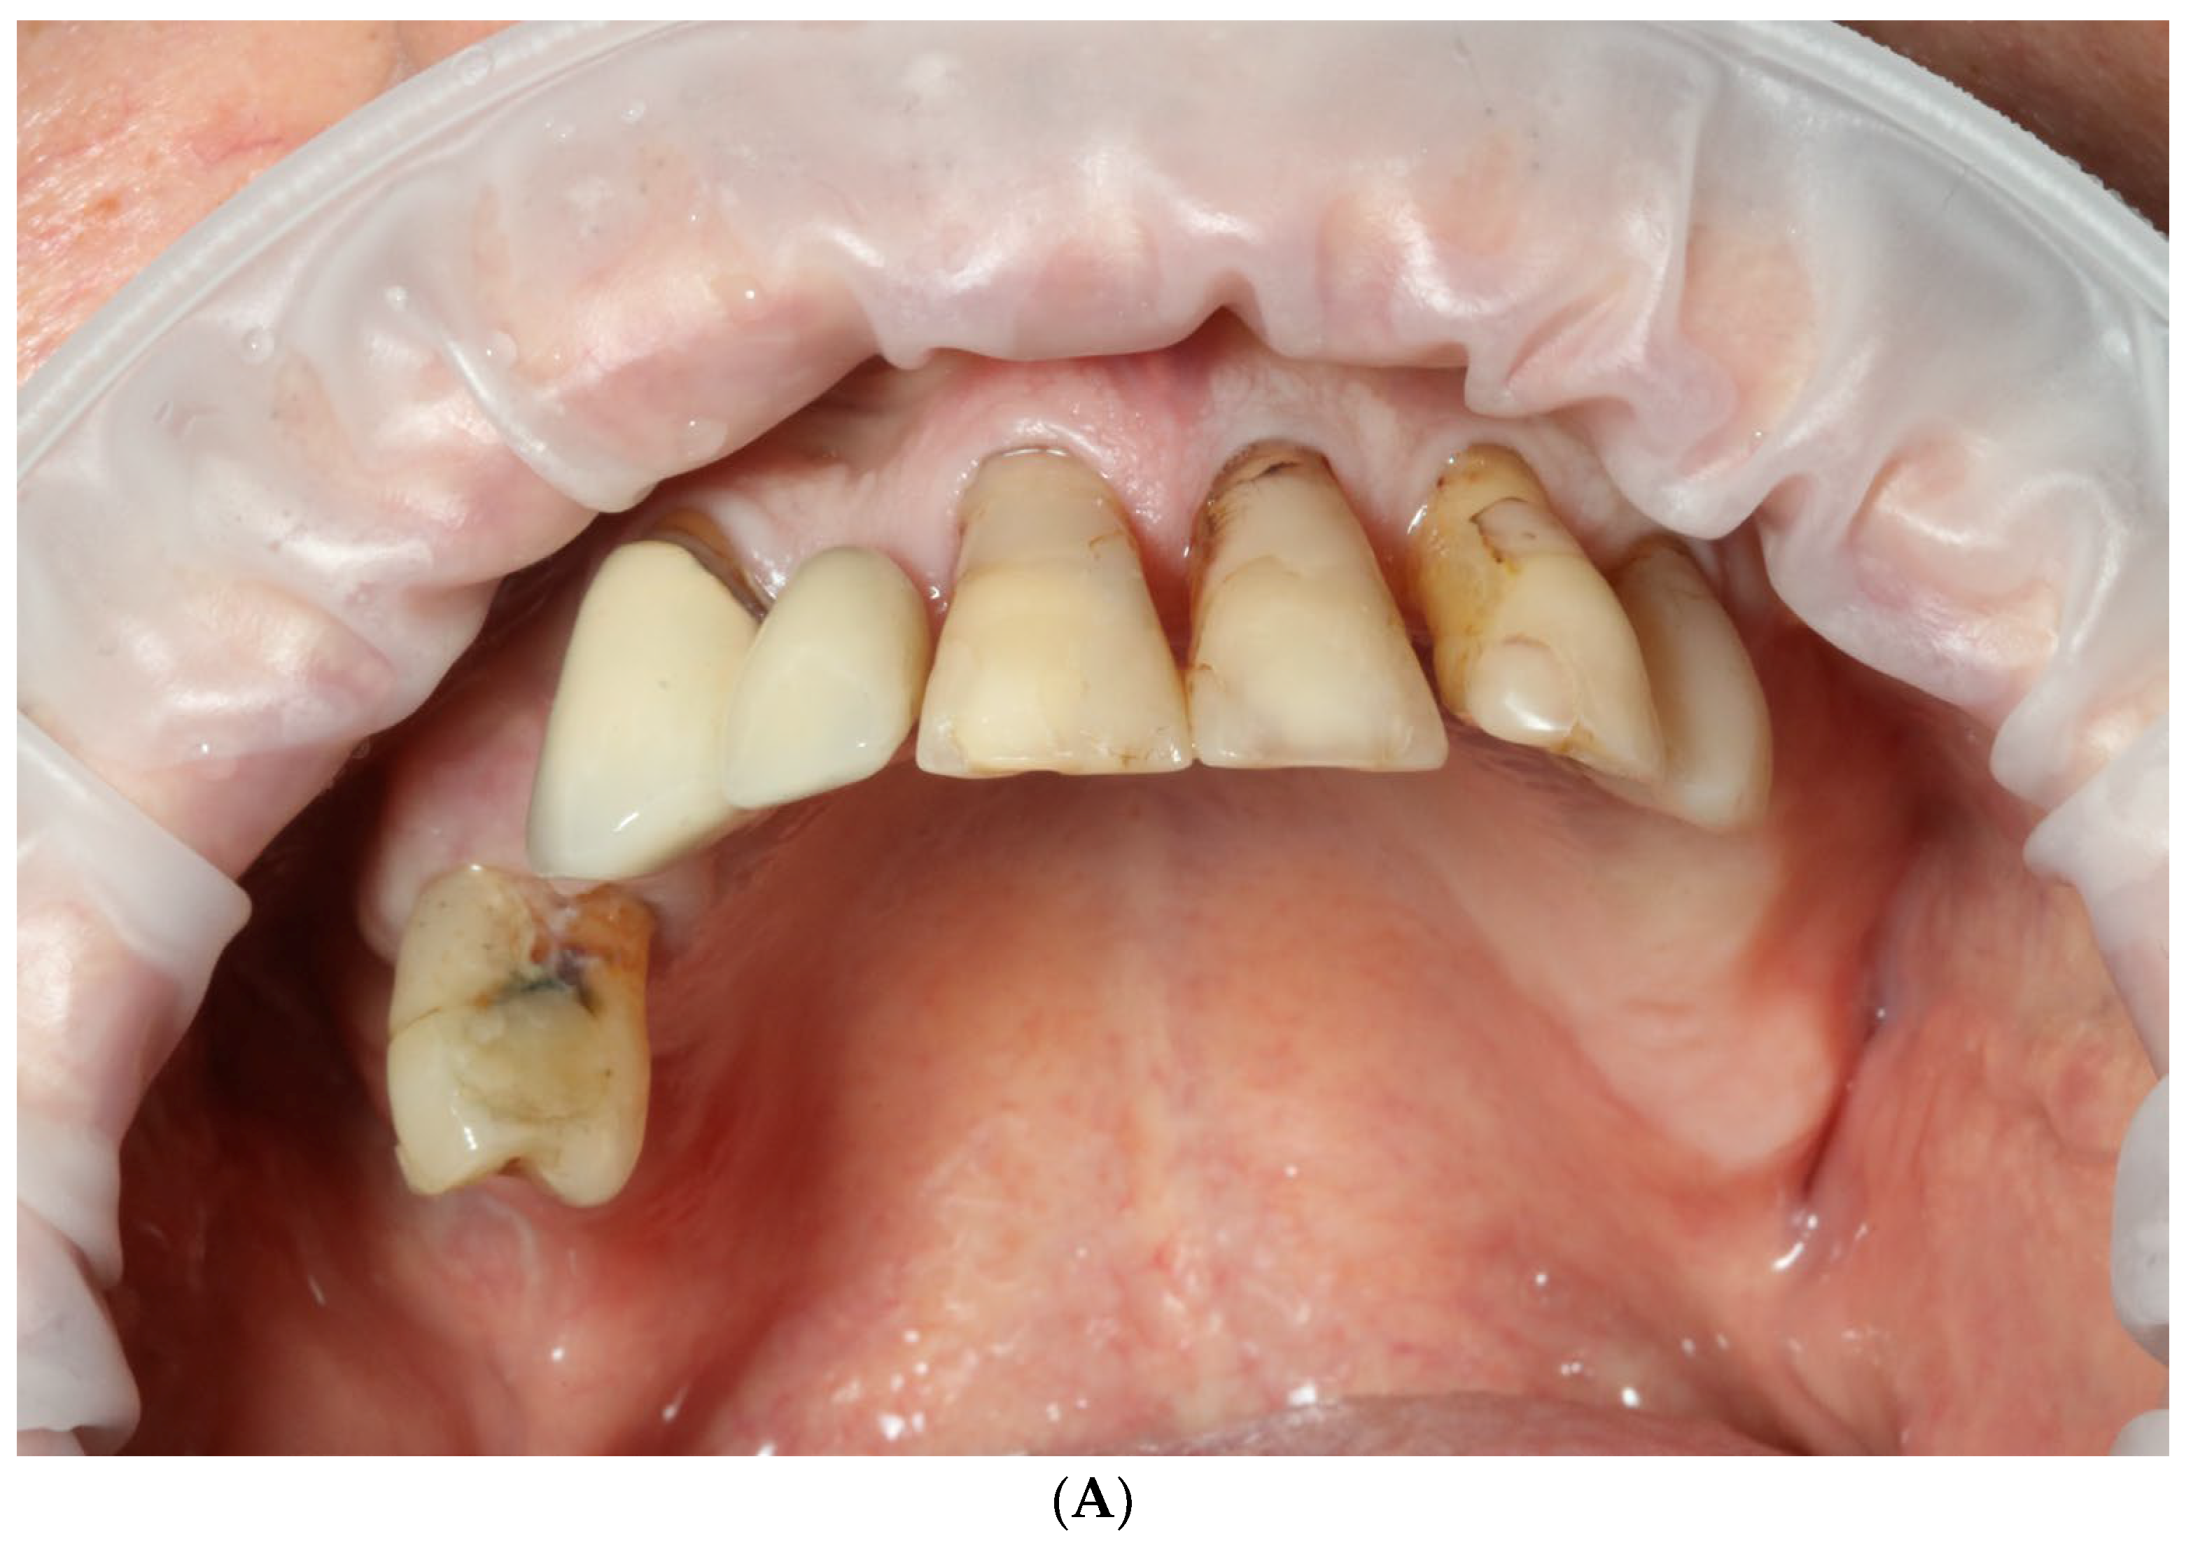

2.1. Patient Information and Clinical Findings

2.2.1. Stage I